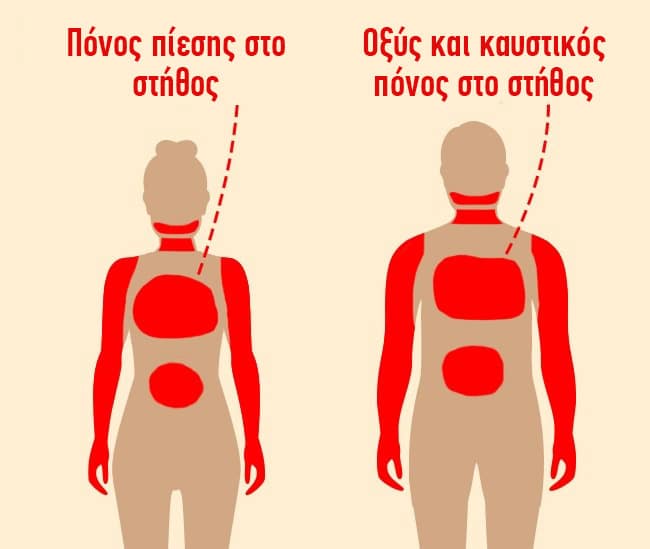

#1 Πόνοι στο στήθος

Άντρες και γυναίκες βιώνουν πόνους στο στήθος σε διάφορες εντάσεις και μορφές. Για τους άντρες, αυτό το σύμπτωμα αποτελεί το σημαντικότερο πρώιμο σημάδι μιας επερχόμενης καρδιακής προσβολής και δεν θα πρέπει να αγνοηθεί. Από την άλλη, εμφανίζεται μόνο στο 30% των γυναικών.

Περιγραφή: Ο πόνος στο στήθος μπορεί να επεκταθεί σε δυσάρεστες αισθήσεις και στα δύο χέρια (πιο συχνά στο αριστερό), το κάτω σαγόνι, τον αυχένα, τους ώμους ή το στομάχι. Μπορεί να έχει προσωρινό ή μόνιμο χαρακτήρα.